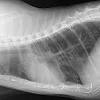

How To Tell If Cat Has Lung Cancer / Cat Flu Upper Respiratory Infection International Cat Care - Vomiting and diarrhea are common signs of gastrointestinal lymphoma.. Panting, abdominal effort when breathing, wheezing, coughing, and inability to exercise are also signs of lung tumours in cats. Because many cats and dogs may not show obvious signs of cancer pain and also tend to hide pain as a protective mechanism, identifying the degree of pain and the amount of suffering can be very difficult. The cancer has matatizied in two toes on his right foot. Look out for any of the following symptoms if you suspect your cat may have lung cancer: A ct scan is a very commonly used tool for oncologists who deal with all types of cancer, including common and uncommon types of lung cancer.

Other symptoms of lung cancer include: Siamese cats have also been found to be at twice the risk for this type of cancer than other breeds, but the reason for this is still unknown. A computed tomography, commonly referred to as a cat or ct scan,. Adenocarcinoma is a malignant neoplasm, making up about 75 percent of all primary lung tumors in cats. Sudden weight gain or bloating can be a sign of cat cancer, specifically gi, in cats.

However, a definitive diagnosis of lung cancer requires a sample of tissue (biopsy). Can a ct scan tell if a patient has lung cancer? Coughing will usually be accompanied by additional symptoms if cancer is present, but it's worth keeping an eye on your cat if he has a chronic cough. Siamese cats have also been found to be at twice the risk for this type of cancer than other breeds, but the reason for this is still unknown. Signs of fluid in a cats lungs may include: Lung cancer symptoms during the early stages of the disease, lung cancer will manifest itself as a common feline upper respiratory infection. A diagnosis of cancer cannot be made on symptoms alone. The cat will have a dry cough and will be less active. Other symptoms of lung cancer include: He has a great appitite and is not compromised, yet. Different cancers have different symptoms. You don't have any signs or symptoms of lung cancer. These tumours develop in the lining or inner surface of an organ and usually has glandular properties.

Lung cancer symptoms during the early stages of the disease, lung cancer will manifest itself as a common feline upper respiratory infection. A lung nodule (or mass) is a small abnormal area that is sometimes found during a ct scan of the chest. A ct scan is a very commonly used tool for oncologists who deal with all types of cancer, including common and uncommon types of lung cancer. Some tumors (e.g., oral cancer) first spread to a nearby lymph node, which can be suspected (but never proven) by doing a thorough physical exam on your cat. Vomiting and diarrhea are common signs of gastrointestinal lymphoma. Other tumors (e.g., malignant melanoma) most often spread to the lungs, which act as a filter for tiny cancer cells. Lung tumors (feline lung tumors): Not all cancers show up on ct scans. But it can also be a potential harbinger of cancer. For example, certain breathing problems and coughing are surprisingly uncommon; Increased respiratory rate (>40 breaths per minute) increased respiratory effort (working harder to take breaths) This is not a common type of tumor in cats. Less than a third of cats diagnosed with lung cancer have breathing problems.

Your Dog Or Cat Has Been Diagnosed With Cancer Now What from vetstreet-brightspot.s3.amazonaws.com Other tumors (e.g., malignant melanoma) most often spread to the lungs, which act as a filter for tiny cancer cells. For tumors in the belly area, an ultrasound allows your vet to examine the whole area. Vomiting and diarrhea are common signs of gastrointestinal lymphoma. Different cancers have different symptoms. This type of cancer is rare in cats, and accounts for less than 1% of all tumours. Fluid accumulation around the lungs (called pleural effusion) is common in cats with primary lung tumors. If a cat's heart has become weak, the lungs operate less effectively and less oxygen is pumped into the bloodstream. Some tumors (e.g., oral cancer) first spread to a nearby lymph node, which can be suspected (but never proven) by doing a thorough physical exam on your cat.